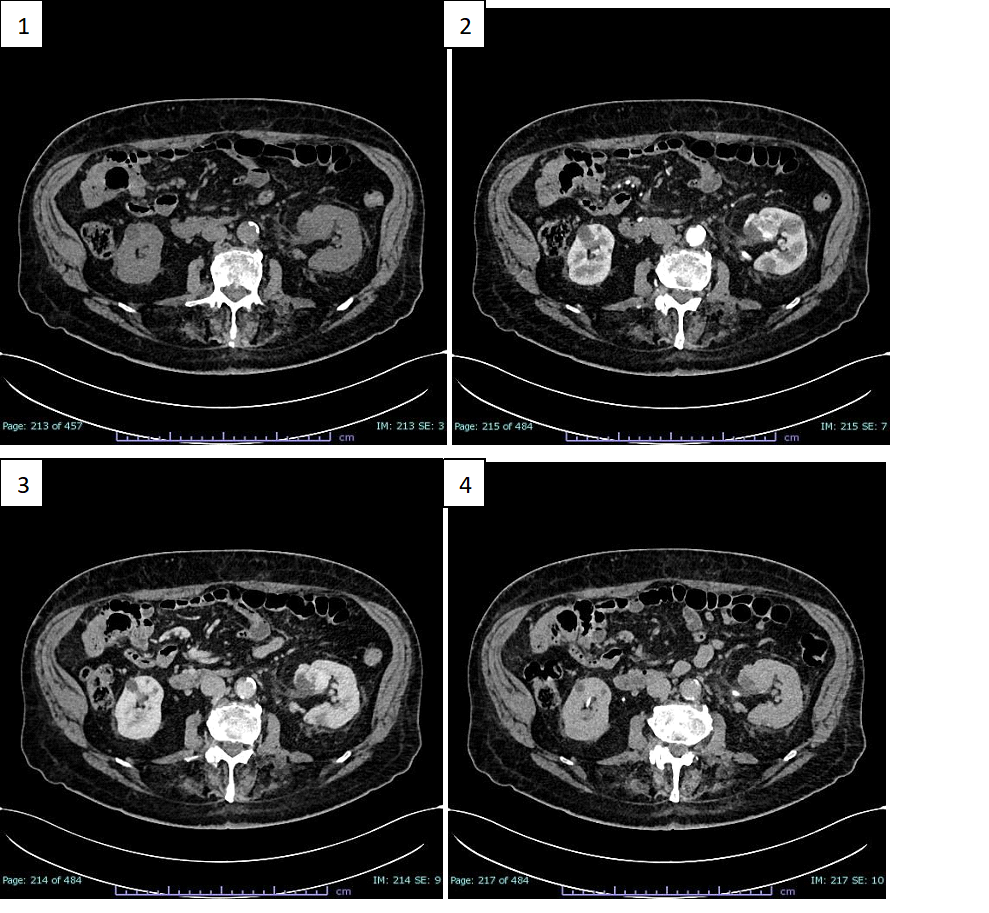

Following this finding, he underwent CT investigation without and with intravenous CM (Figure 1).

An axial CT scan showed an expansive formation with oval morphology in the left renal sinus outlining the organ with dimensions of about 32 x 30 mm, which tended to grow in the connective tissue of the renal sinus, slightly dislocating the inferior calyx group.

In non-enhanced acquisition (Figure 1.1), this formation presented a heterogeneous appearance with average values of HU of 19-20 HU, with negative values with adipose significance in some places, and peripheral areas values of 37-60 HU.

In the arterial phase scans (Figure 1.2), the periphery of the lesion showed a clearly annular and pseudonodular enhancement with a tendency to centripetal filling and densitometric values reaching 230 HU, thus demonstrating a highly representation of vascular tissue component.

In the venous phase (Figure 1.3), the lesion showed a tendency to homogeneous filling with average values up to 130 HU. The lesion showed homogeneously persistent enhancement in late scans (Figure 1.4), with HU values between 50 and 70.

Figure 1

Figure 1: CT scans before and after enhancing with CM. 1) Non enhanced axial CT scan: a

hypodense expansive formation is seen in left renal sinus (32 x 30 mm). 2) Axial CT with CM early arterial phase: the formation shows peripheral annular and pseudonodular enhancement. 3) Axial CT with CM venous phase: the formation shows tendency to homogeneous filling. 4) Axial CT whit CM late phase: the formation shows homogeneously persistent enhancement.

The imaging features reported in the case presentation show a tendency towards heterogeneity, indeed, both methods lean towards a pre-operative diagnosis of malignant lesions. At the CT scan without CM, an inhomogeneous hypointense lesion is evident in the left renal pelvis, at the level of the lower third, which shows uneven density in all its points, varying from punctiform areas with adipose-like densitometric coefficients (from -10 HU to -2 HU), to more frankly solid areas (49-20 HU) and to sections suggesting the presence of vascular components (37-60 HU). These findings are confirmed in subsequent scans enhanced with CM and, in particular, the lesion shows a frank enhancement in the more caudal peripheral portion in the arterial phase (up to 230 HU). In the subsequent portal phase a more homogeneous contrastographic filling of the entire lesion, with values of around 130 HU, was noted confirming the presence of an important hypervascular tissue component. However, the lesion shows no frank signs of invasiveness or compression of the surrounding structures, in the absence of dilation upstream and downstream of the lesion. Furthermore, there are no signs of necrosis or calcifications within the lesion. MRI images also show characteristics of inhomogeneous signal intensity, reflecting its vascular nature, revealing signal hypointensity in T1 sequences, inhomogeneous signal hyperintensity in T2 and poor signal restriction in DWI, indicative of poor cellularity. In line with the literature, our experience confirms the complexity of discriminating against the dyskaryokinetic nature of such a complex lesion with CT investigations, even if supplemented by MRI acquisitions. Thus, even if there are many overlapping features among the entities placed in benign vs. malignant differential diagnosis from the anatomopathological perspective, this diagnostic difficulty appears even more evident to the radiologist's eye. Indeed, it is not surprising that AH is still treated with demolitive approaches, such as total or partial nephrectomy, or more rarely local excision, with the aim of clarifying the nature of the lesion. However, in support of the biologically indolent nature of AH, some limited evidence exists on a small group of patients brought to follow-up which showed no tendency for recurrence or metastasis [3,9].